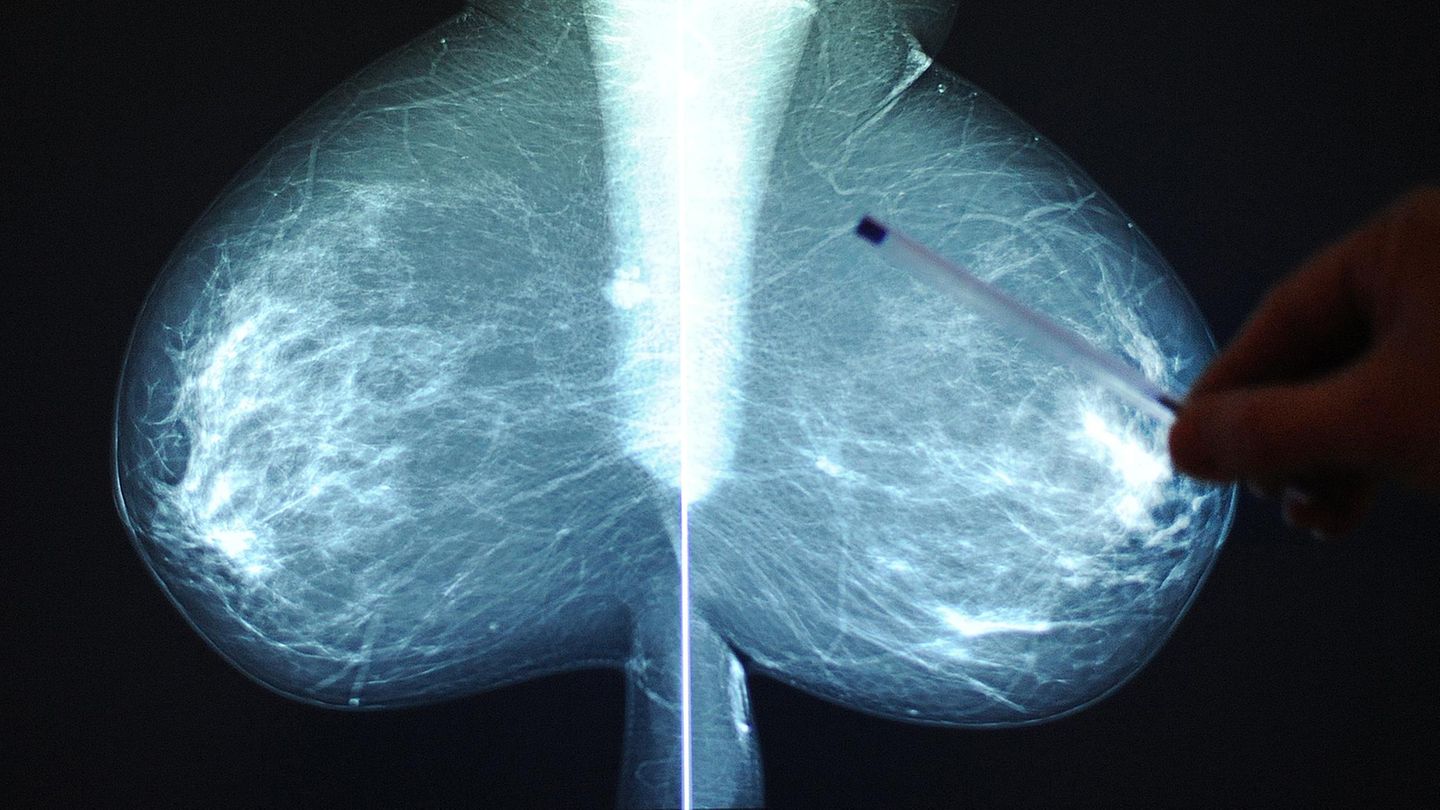

Die Röntgenaufnahme einer Brust während einer Brustkrebsvorsorge im Wiener St. Josef Krankenhaus

© BARBARA GINDL/APA/Picturedesk.com / Picture Alliance